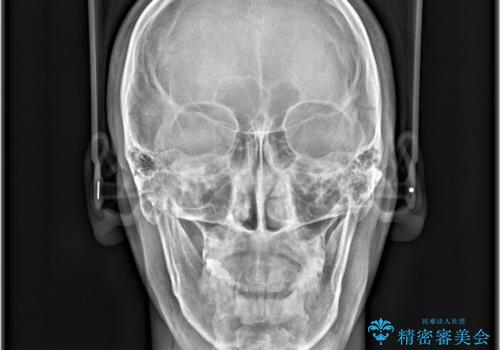

- 「上の前歯の捻じれと下の前歯のでこぼこを治したい」を主訴に来院された患者様です。

矯正検査の結果、非抜歯で矯正可能だったためインビザラインで治療を行いました。

アーチの拡大とIPRで叢生を改善いました。

11ヵ月で矯正を終える事ができ患者様も大変ご満足されていました。